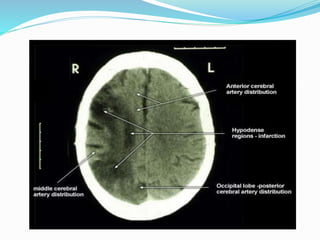

Hypoxic-Ischemic Injury

• The most frequently and severely affected area is the

parietooccipital region at the confluence between the ACA,

MCA, and PCA territories.

• Most common observed on NECT is a low density band at

the interface between major vascular territories.

• The basal ganglia and parasagittal areas are the most

frequent sites.